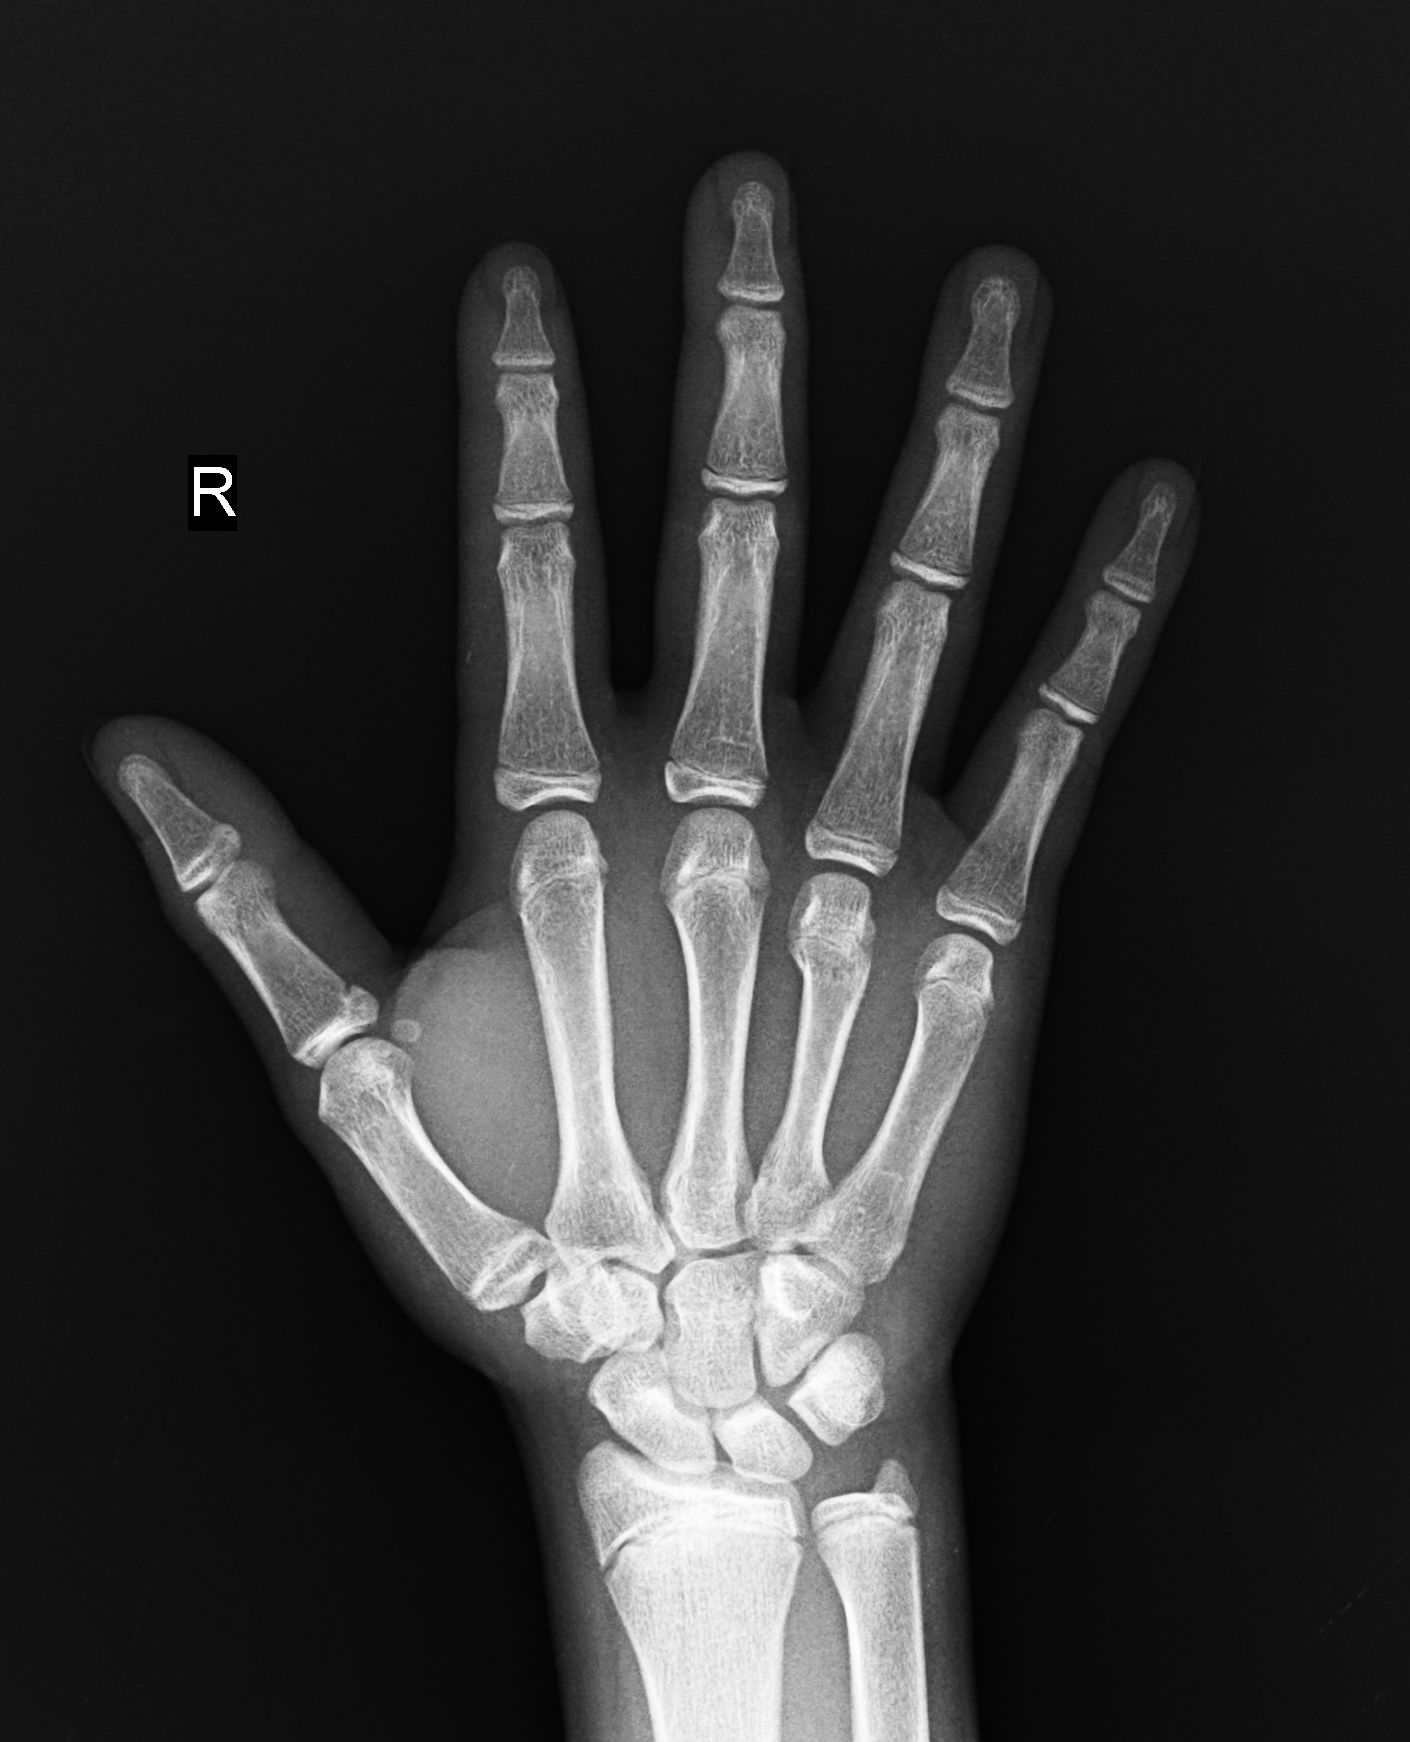

臨床圖片